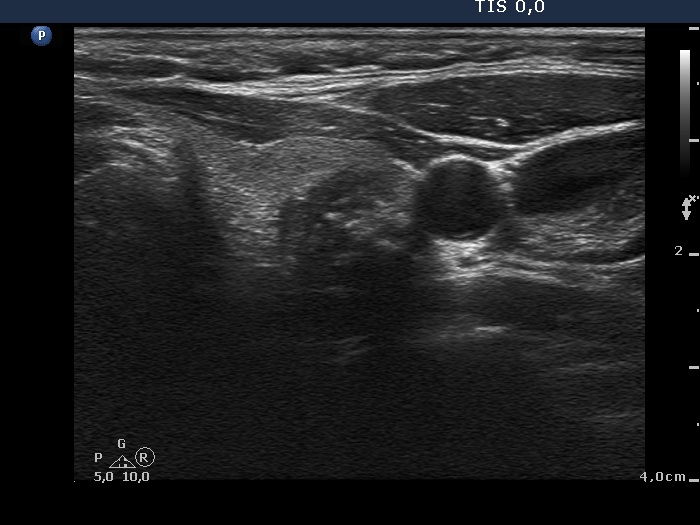

Benign hyperplastic nodule (histological diagnosis) - case 489 |

The nodule had an eggshell calcification.